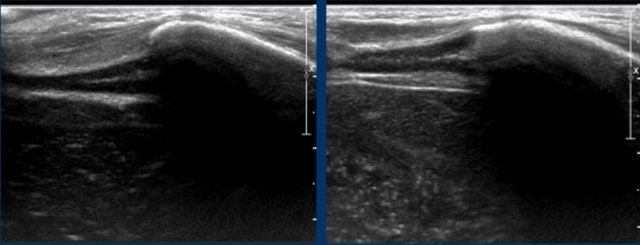

Especially

fractures at the ventral ends of the ribs are challenging.

Ultrasonography is helpful in detecting dislocation at the ventral costo-chondral junction.

Images

Child evaluated for soft tissue mass in costchondral region. The ultrasound shows soft tissue swelling (yellow arrows), chondral part of rib (red arrow) disrupted from bony part (orange arrow) of rib. The Initial chest film was negative. Chest film 2 weeks later showed fractures.